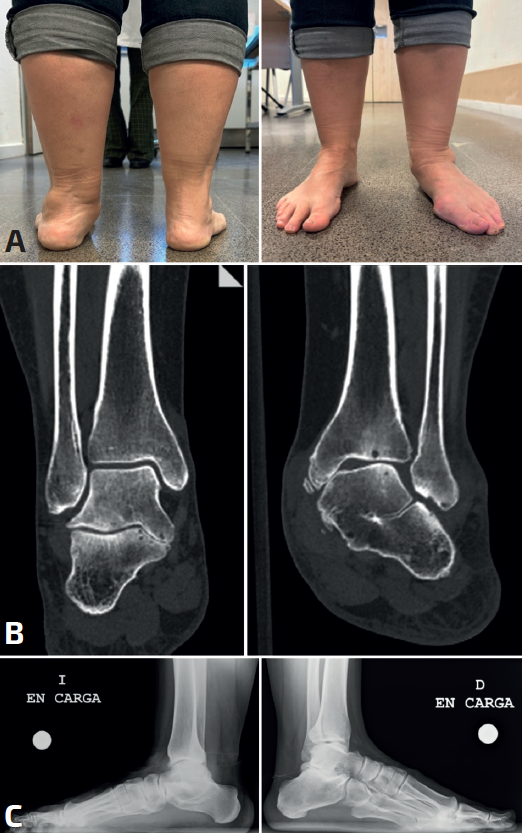

Por otro lado, debido al estudio de referencia de Harris(4), se cree que las coaliciones se asocian universalmente con la deformidad del pie plano. De este modo, todo pie plano infantil sintomático se trataría de una coalición. Sin embargo, solo alrededor de la mitad de las coaliciones se asocian con el pie plano(22) e incluso pueden asociarse con una deformidad del pie cavo(7,23,24,25)(Figura 1).

Debemos ver caminar al paciente, el examen físico puede revelar un retropié rígido en valgo, con rotación externa y abducción del antepié, aunque un retropié neutro o en varo no excluirá el diagnóstico(25). Es importante registrar para el tratamiento posterior la posición relativa del calcáneo.

El dolor puede situarse a la palpación tanto sobre el seno del tarso como en la carilla medial, justo distal al maléolo medial. En todos los tipos de coalición tarsiana se observa comúnmente una reducción de la eversión e inversión pasivas. Aunque es vital comparar los hallazgos con el pie contralateral, debemos tener siempre un alto índice de sospecha de posibles coaliciones bilaterales y la exploración bilateral es obligatoria. El espasmo de los músculos peroneos asociado con dolor a la inversión forzada sugiere una coalición, pero no es diagnóstico(2,29).

Toda rigidez del retropié debe hacernos sospechar de una posible coalición. Las coaliciones TC de la faceta media crean la mayor pérdida de movimiento subastragalina y la deformidad en valgo más obvia(2,3,30).